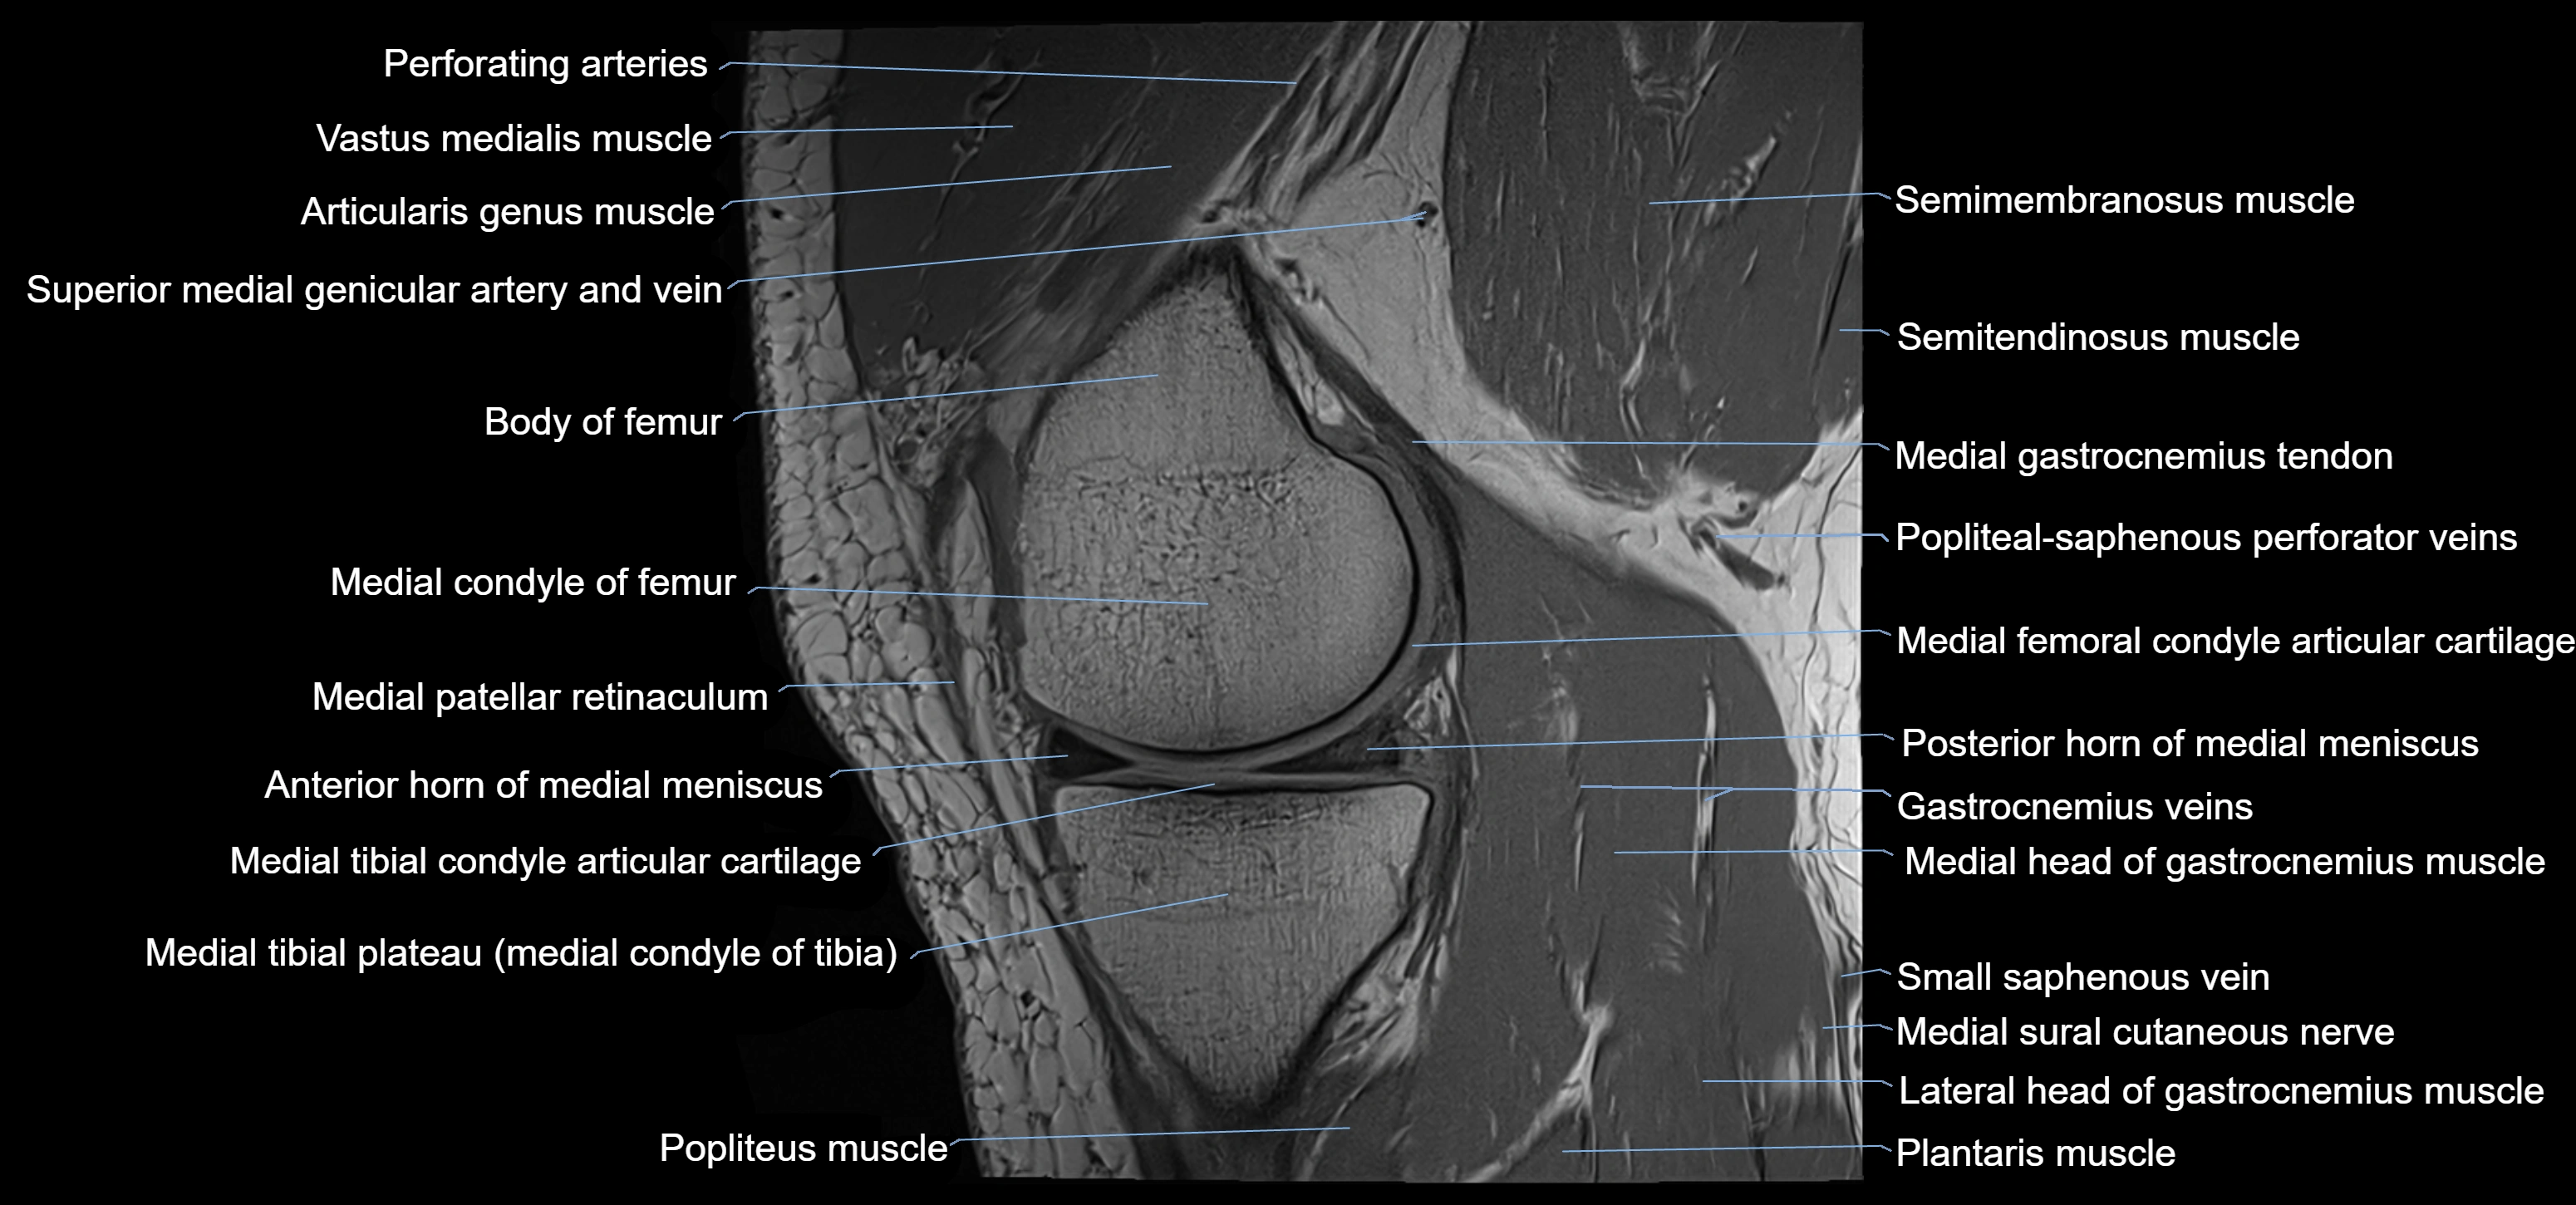

- Anterior horn of medial meniscus

- Medial condyle of femur

- Medial condyle of tibia

- Medial gastrocnemius tendon

- Medial head of gastrocnemius muscle

- Medial meniscus

- Medial patellar retinaculum

- Medial tibial plateau

- Perforating Arteries (Knee joint)

- Popliteal–Saphenous perforating veins

- Popliteus muscle

- Posterior horn of medial meniscus

- Semimembranosus muscle

- Semitendinosus muscle

- Superior medial genicular artery